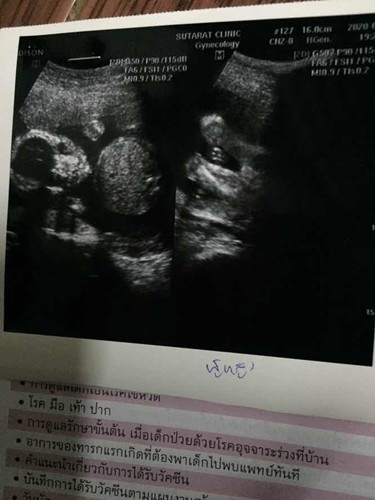

สอบถามแม่ๆหน่อยค่ะหมอบอกว่าเป็นผู้หญิง100% แต่ทำไหมมีแต่คนทักว่าจะได้ผู้ชายค่ะแม่บ้านนี้ท้องแรกดูไม่เปนค่ะ

เชื่อหมอค่ะ อัลตร้าซาวด์ดีที่สุด